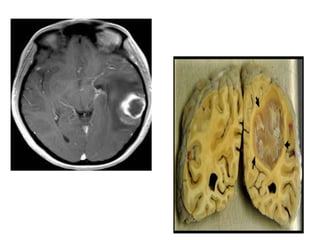

• 12.

Brain Tumors • Theadvent of MRI scans has made the diagnosis and the determination of the extent of disease more accurate. • tumors, functional mapping and electrocorticography, which allow pre- and intraoperative differentiation of normal and tumor tissue, the use of ultrasonic aspirators and neuroendoscopy, have all improved the results of neurosurgical intervention. • coupled with the use of various chemotherapy regimens, have resulted in considerable improvements in outcome for some. • This field, however, still remains an area begging for a better understanding of the optimum management of these devastating and often fatal tumors.